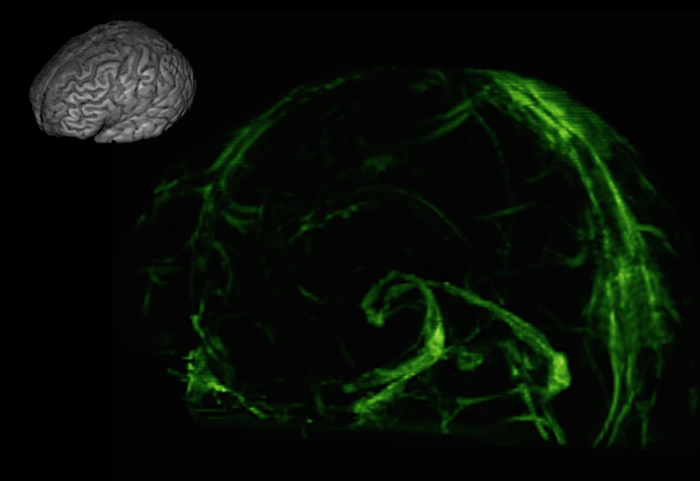

You are now among the first people to see the brain’s lymphatic system. The vessels in the photo above transport fluid that is likely crucial to metabolic and inflammatory processes. Until now, no one knew for sure that they existed.

Doctors practicing today have been taught that there are no lymphatic vessels inside the skull. Those deep-purple vessels were seen for the first time in images published this week by researchers at the U.S. National Institute of Neurological Disorders and Stroke.

His team’s discovery, though, not only shows that the vessels exist in people, but just how elaborate the system is.

The lymph vessels probably escaped detection because they’re inside a thick membrane, the dura mater, which is the consistency of leather. They run alongside blood vessels that are much larger, and on MRI the signal that creates the images is dominated by the blood vessels.